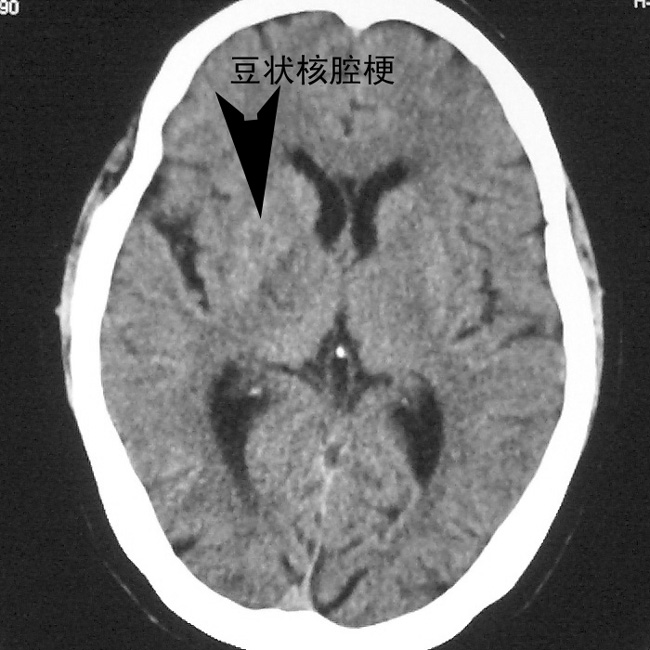

f,70y,口角歪斜、流涎、吐词不清三天

左侧大脑基底节区点状低密度影,边缘清楚,左侧腔梗或软化灶,没什么问题啊?

双侧多发腔梗

右侧基底,左侧半卵圆中心腔梗

1、右侧基底,左侧半卵圆中心腔梗。2脑萎缩。

左侧半卵圆中心,右侧基底节腔梗。再加个脑萎缩吧